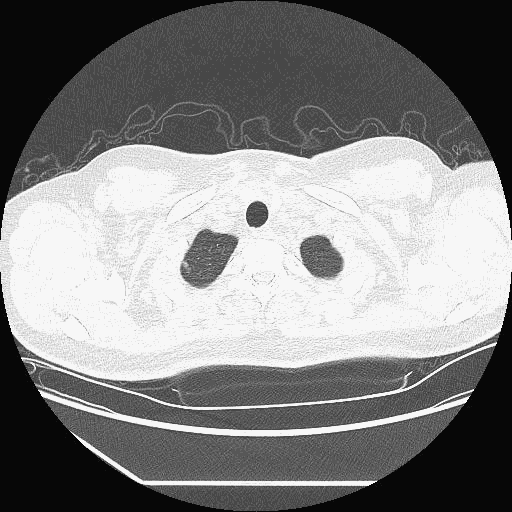

入本院时CT.gif